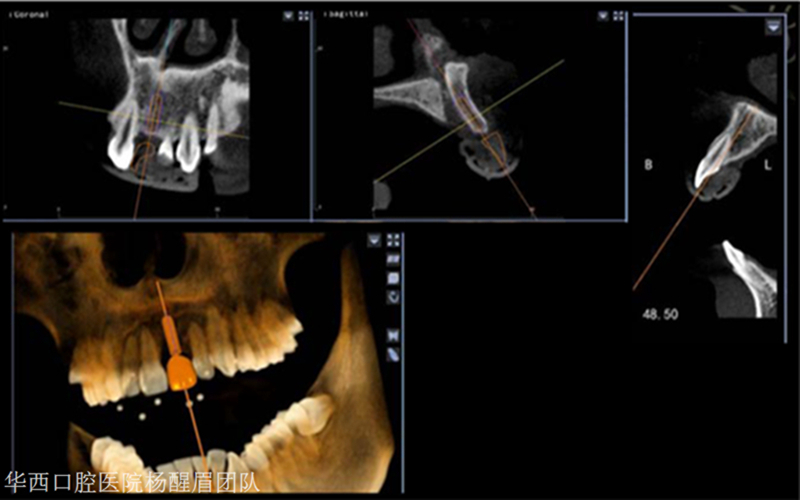

今天小迪為大家?guī)硪焕扇A西口腔的楊醒眉教授主刀, 避免骨劈開及切牙管、完美的前牙美學區(qū)數(shù)字化種植手術(shù)的病例分享。

使用迪凱爾易植美主動式紅外光導航設(shè)備進行導航手術(shù)

根據(jù)術(shù)前設(shè)計的種植方案開展手術(shù)

1.逐級備洞 2.術(shù)中,導航對種植區(qū)域位點,角度及深度實時引導 3.根據(jù)導航方案完成擴孔工作

植入種植體,根據(jù)術(shù)前方案,植體位點偏舌側(cè)